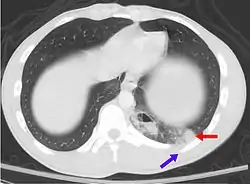

- Pulmonary contusion